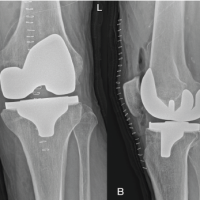

Recognizing the bilateral AFFs and the imminent risk of a right-sided fracture, prophylactic intramedullary nailing was performed on the right femur (Fig. 3), based on the current clinical evidence. This approach also facilitated positioning for subsequent fracture reduction and reconstruction nailing of the left femur (Fig. 4), conducted 2 days later. The postoperative course was uneventful. Bisphosphonate therapy was discontinued, and the patient was started on teriparatide injections, calcium, and vitamin D supplementation. After satisfactory post-operative X-rays (Fig. 5), full weight-bearing mobilization with walker support was initiated.

Six weeks into rehabilitation, during one of the mobilization sessions, the patient reported pain at the site of prophylactic nailing in the right femur. Radiographs revealed a minimally displaced fracture in the proximal third of the right femur (Fig. 6). Conservative management was pursued due to the absence of significant displacement or angulation, which was probably due to the prophylactic nail in situ. Mobilization was restricted to bedside exercises for 6 weeks, followed by a gradual return to full weight-bearing activity. There was no complaint of worsening of pain or any other symptoms with this conservative approach. With regular clinical and radiological follow-ups, the patient demonstrated progressive healing, transitioning to single crutch-assisted ambulation by 6 months. One-year post-surgery, complete bilateral fracture consolidation was observed (Fig. 7), and the patient achieved unaided, pain-free mobility. She is still under follow-up and is doing well, with no further symptoms so far.